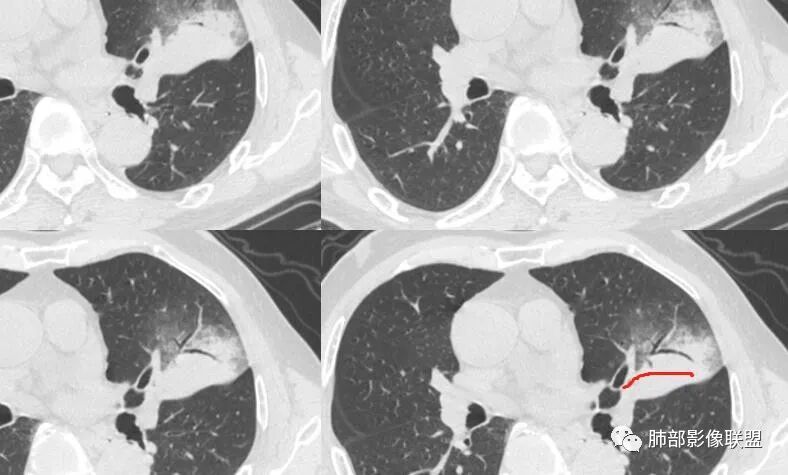

我标示一下,尖后段搭到一部分,前段也占了一点点。

南边:

主体在舌段

有占位效应吗?

有,斜裂局部膨隆

边缘膨隆,叶间裂有局部膨出下坠

有膨隆+收缩

支气管?

支气管外面堵了,近端有扩张

有堵塞,有狭窄

中远端堵塞,堵塞端圆钝